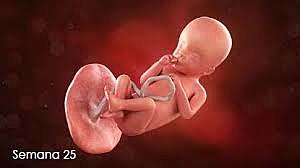

• Semana 25

Semana 25

-Las neuronas se interconectan

-Comienza a captar olores

-Mide alrededor de 20 centímetros y pesa unos 600 gramos.

-No para de moverse dentro del útero materno.